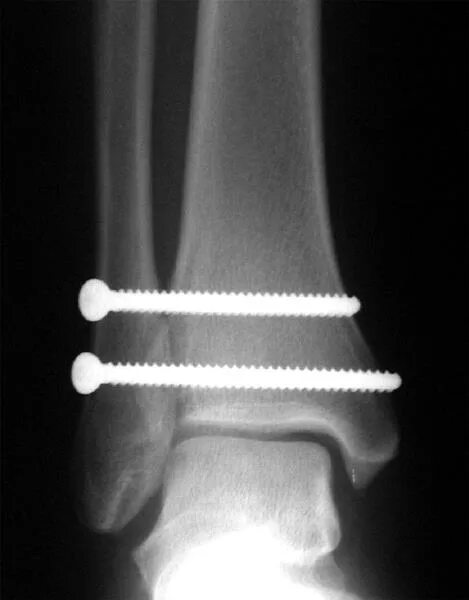

После остеосинтеза лодыжек